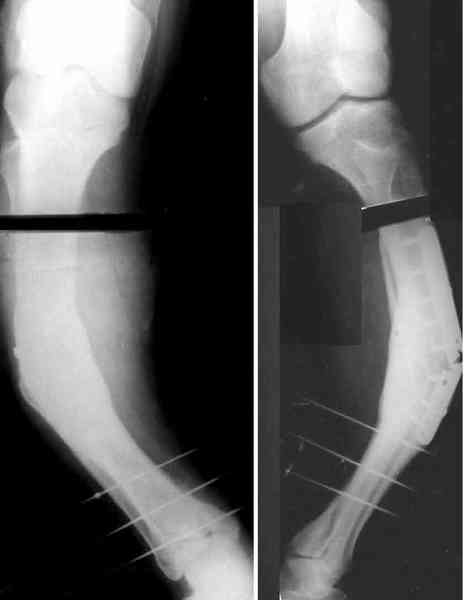

Для продолжения темы - несколько картинок.

Пациент 30 лет, лет пять назад оперирован по поводу перелома голени пластиной. Находясь на героине, нарушил режим, пошел, сломал и ногу и

пластину, но перелом сросся.

В приложении - внешний вид и рентген.

Мнения?

Лукавить не буду, я его уже вылечил. Но применил немного необычную тактику по отношению к пластине - результат после обсуждения...

AC> Аппарат с шарнирами, чрескожная остеотомия, устранение угла.

Александр, как раз уровень остеотомии подробнее - на вершине деформации? Там Сломанная пластина.

Там не винты (может, плохо видно), а сломанная пластина, вросшая в кость.

a> Александр, как раз уровень остеотомии подробнее - на вершине

a> деформации? Там Сломанная пластина.

Ну, например, на уровне перелома пластинки. Можно пересечь часть кости, не прилежащую к пластинке, затем надломить остальное.

a> Там не винты (может, плохо видно), а сломанная пластина, вросшая в

a> кость.

Пластинку и винты мне удалось разглядеть только на профильной проекции, точнее, трехчетвертной, судя по виду коленного сустава (правый снимок). На фасной - вообще не могу разобрать, где она :( Но, в конце концов, можно и не видя ее сказать, что уровень остеотомии может быть и другим, ниже или выше пластинки, придется только компенсировать смещение по ширине, которое появится при полном устранении угла не на вершине.